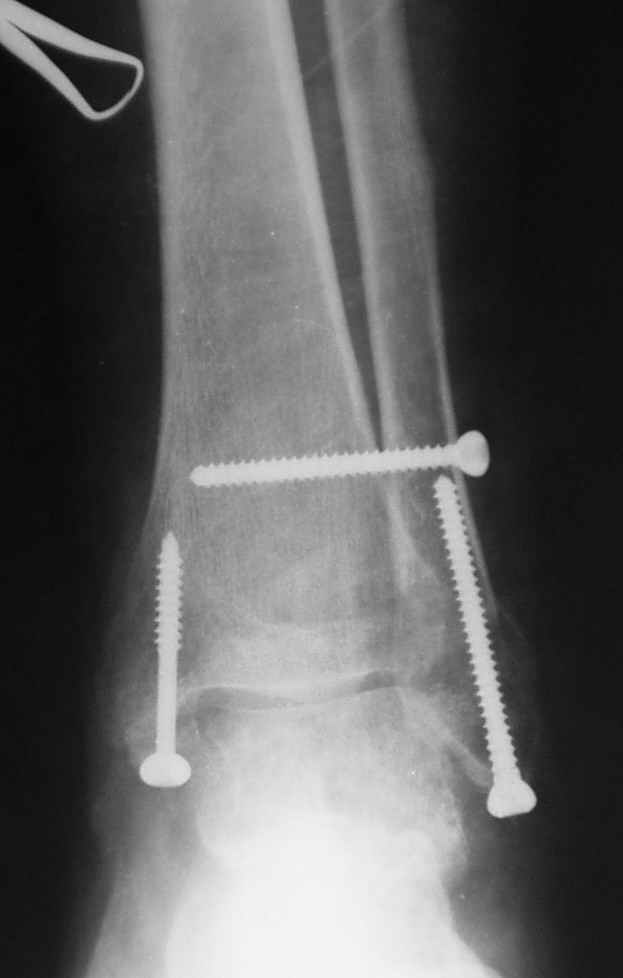

Ниже рентгенограммы

Операция 29 июля

Через месяц

Боковой через месяц

15 ноября прямой

15 ноября боковой

15 ноября трехчетвертной

12 января прямой

12 января боковой

12 января трехчетвертной

Риторический вопрос - в каком руководстве рекомендован такой способ остеосинтеза наружной лодыжки?

Очевидно, такой результат операции был запрограммирован. При невосстановленной длине и практически нефиксированной малоберцовой кости (этот кортикальный винт - как карандаш в стакане), при неустраненном подвывихе, невправленной и тоже нефиксированной внутренней лодыжке нет стабильной вилки сустава. Если такую операцию сделать даже сразу, а не через 4 месяца, то результат ожидаем

тот же.

Вообще говоря, такое повреждение вполне успешно можно лечить без операции - если 6 недель подержать в гипсовом "сапожке" с хорошо устраненным подвывихом. Вероятное несращение внутренней лодыжки не обязательно компрометирует результат.

Ну а уж если выбран остеосинтез - нначать надо было с репозиции малоберцовой кости с точным восстановлением длины, с фиксацией треть-трубчатой пластиной по задней поверхности. Позиционный винт

избыточен - повреждение практически подсиндесмозное. А если бы

действительно было повреждение синдесмоза - в 4 месяца позиционный винт - не решение. Внутренню лодыжку такую - надо было бы спицами и проволочной петлей. Извините за эти банальности.

Вариант с артродезом уже обсудили. Хотя, после увиденых снимков, пессимизм насчет восстановительной операции у меня, например, несколько уменьшился. Особенного уж какого-то остеопороза не видно даже на январских снимках. Можно черед мини-доступы убрать винты, аппаратом вправить малоберцовую кость, устранить подвывих стопы. Ну а дальше фиксировать малоберцовую пластиной сзади. А может, и напряженной Y-спицей попробовать - Анатолий Федорович, как Вы полагаете? Внутреннюю - то, что осталось, если уже не получится сделать спицами и проволокой, то что-то типа пластики дельтовидной связки. А может, и не трогать ее вовсе... В общем, выбор непростой,

много факторов надо взвесить.

Если до сих ничего не сделано, с артродезом сустава в данный момент я бы повременил, на выставленных январских снимках хорошо сохранившийся сустав, а в "мортиз" (трехчетвертной) и на боковых снимках не менее 5 мм укорочение малоберцовой кости. Косые переломы лучше фиксировать пластинами, как то мы разбирали случай, где было отмечено, что это закон "таранная кость всегда следует за малоберцовой".

С подобным случаем приходилось сталкиваться у гормонозависимого пациента с 4 месячным подобным переломом после безуспешного лечения в аппарате Илизарова. Вальгусная стопа, остеопороз, диастаз в медиальной лодыжке. Произвел открытую репозицию мед лодыжки, синтез тяговым винтом 3.5 мм из титана, костную пластику спонгиозой, до 2 см куб из надлодыжечной зоны. Затем остеотомия по линии перелома малоберцовой кости узким долотом из 0.5 см доступа и ручная коррекция вальгуса . Блокирующий винт через обе кости. Остеосинтез по MIPO технологии пластиной 1-3 трубки. Внешней фиксации не применялось, перелом сросся за три месяца. Согласен с д-ром Кульжановым, без пластины в подобных случаях не обойтись.